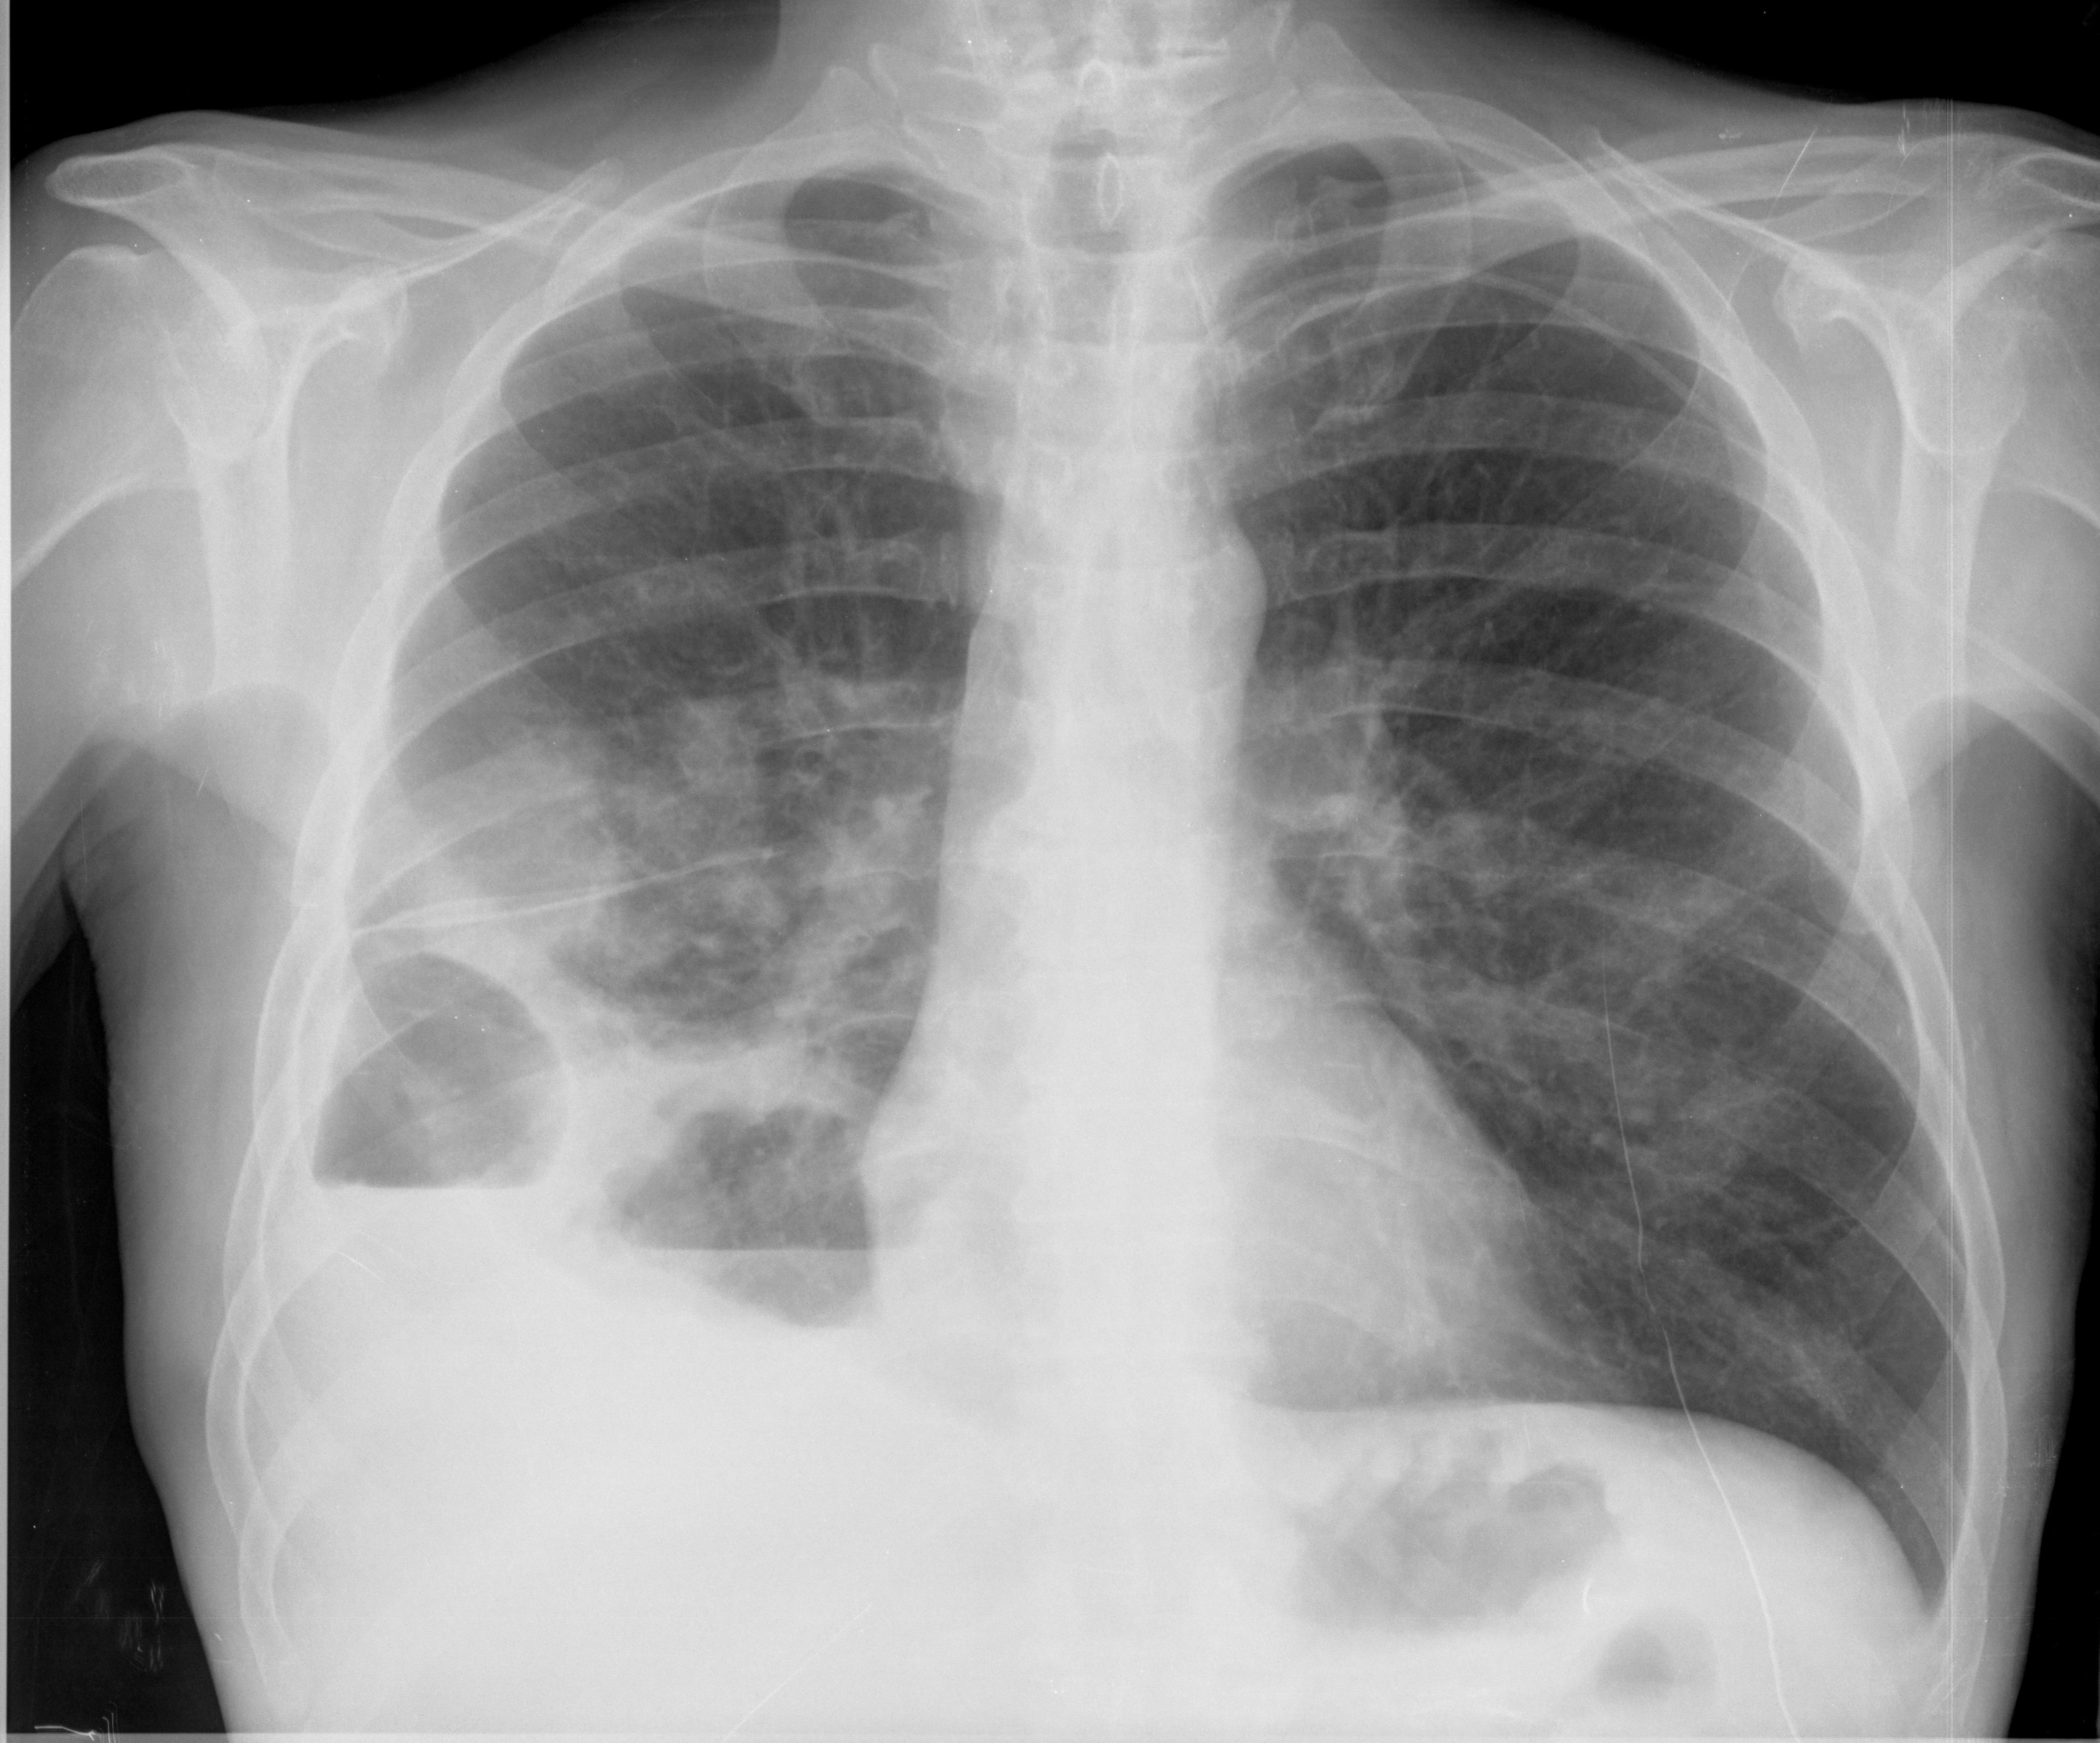

Paciente que ingresa en urgencias por cuadro de fiebre, tos y espectoración. Leucocitosis 16500.

Se realiza radiografía torácica, 2 proyeciones, PA y lateral:

¿Cual es el encapsulado pleural y cual es la cavidad parenquimatosa?